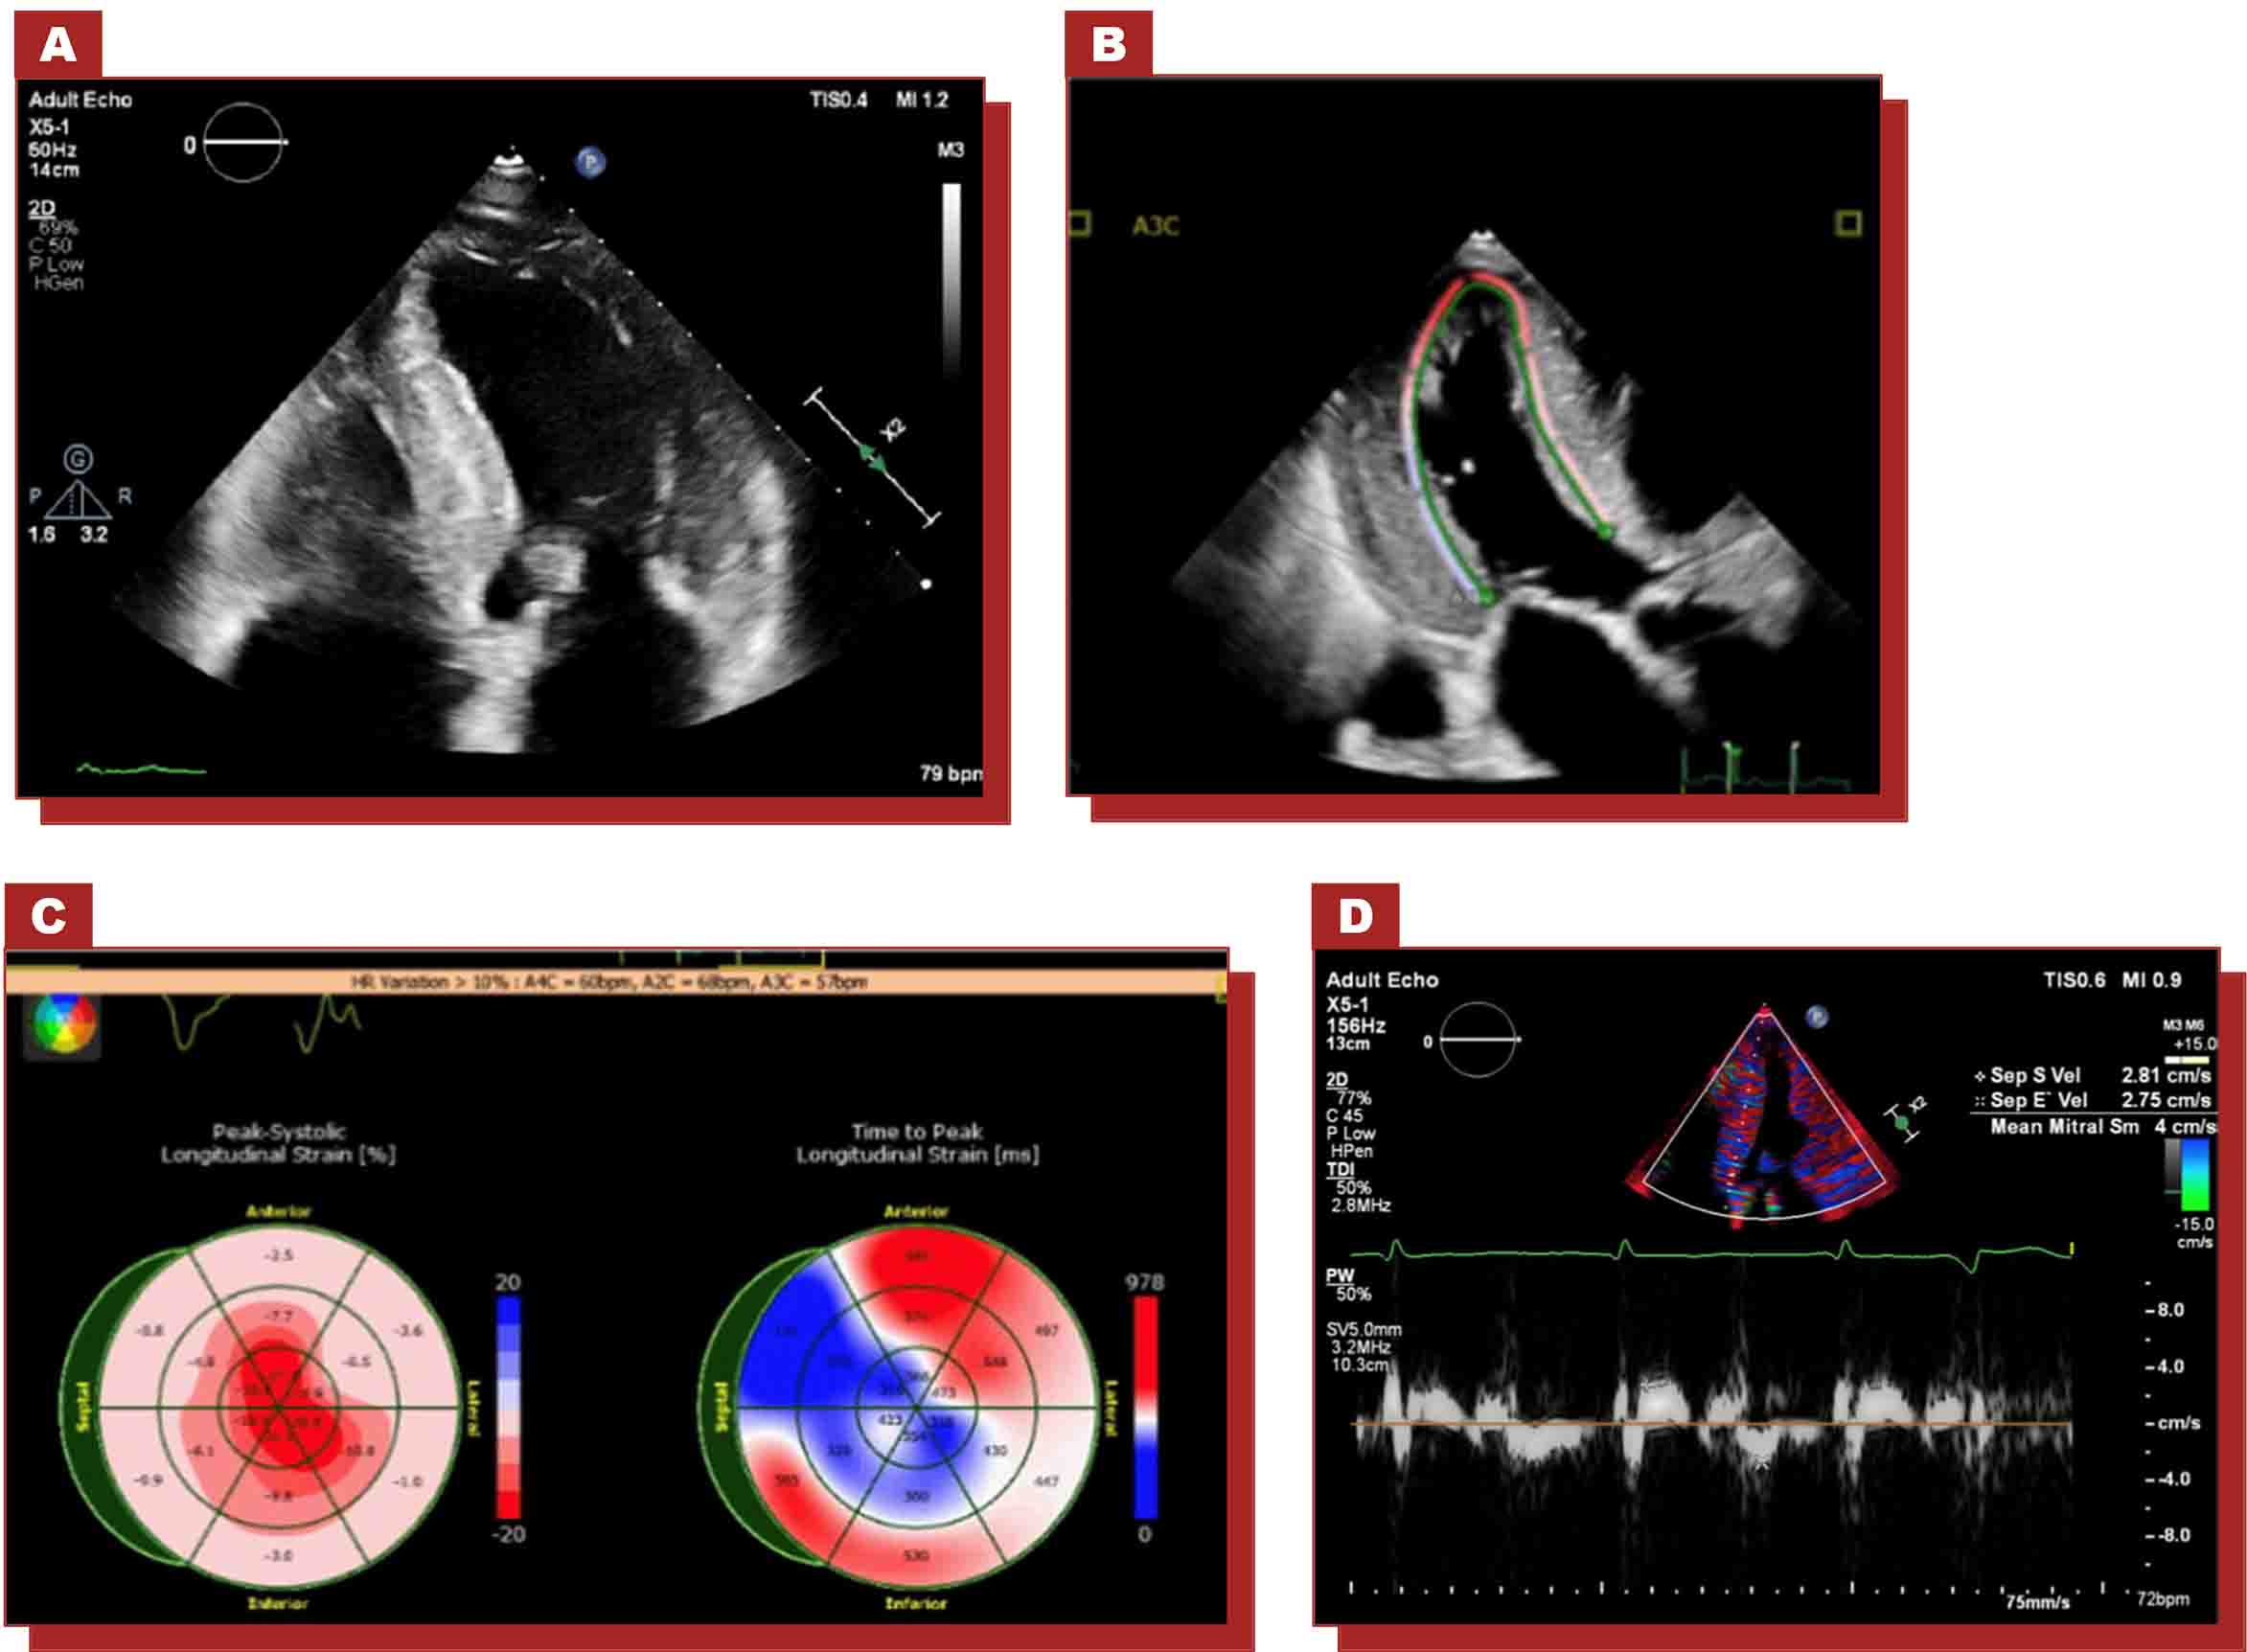

ECO4

- Fenotipo hipertrófico con rasgos infiltrativos

- Llenado restrictivo del VI con engrosamiento de la pared del VD

- Bajo e′ septal o lateral

- Disminución del strain longitudinal global